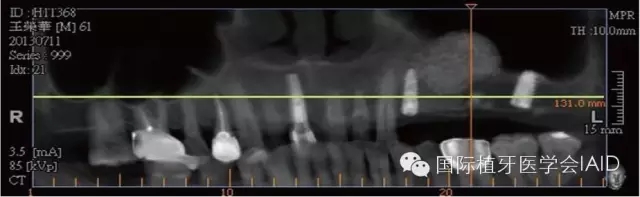

在植牙手術(shù)執(zhí)行之前,需要進行全口檢查與軟硬組織的評估??谕馐嗄P团ccone beam CT資料搜集有助于治療計劃的擬定。在石膏模型上進行diagnostic wax up有助于決定植體上假牙前后關(guān)系、頰舌側(cè)位置、咬合高度、及植體與植體上假牙的高度比例。使用Cone beam CT(CBCT)可以容易了解手術(shù)區(qū)硬組織條件,如Septum、骨頭高度及寬度、骨頭密度、神經(jīng)血管位置等。分析以上數(shù)據(jù)后,較容易得到可預(yù)期性的結(jié)果。

初期穩(wěn)定度在第一及第二類型的案例(>9mm; 6mm-9mm) 可以較容易達到,故通常以crestal approach進行手術(shù)。Lateral window術(shù)式在第三型(3mm-6mm)較被建議。 若是前三個類型的初期穩(wěn)定度達到35Mpa,可以考慮當次放置植體。若骨頭條件屬于第四型(<3mm),Lateral approach 比較建議使用,而植體可考慮等到Grafted Bone較成熟時再置入。(Fig. 1 & 2)術(shù)式的選擇與骨頭高度有密切的關(guān)系,當骨頭垂直高度小于3 mm(于兩顆植體中),植體應(yīng)考慮 Bone graft穩(wěn)定后再植入。